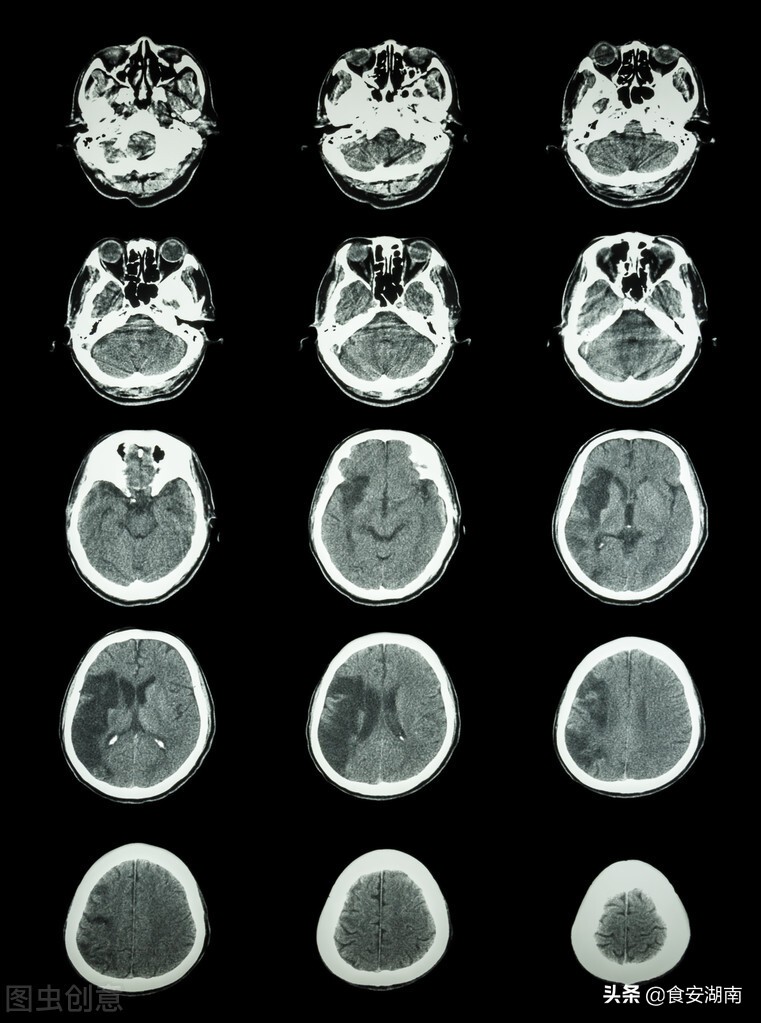

比如说脑卒中危害性非常大,就是不管是脑出血还是脑梗,这个致残率非常高,如果说就是说就是那个就是包括像我们大的这个就是残疾人康复的这个系统当中其实有很多一部分都是因为神经损伤而导致后面残疾的生带着残疾正常生活的,其他的包括脑外伤起的损伤,还有这些肿瘤,这些都是一个比较常见的疾病。